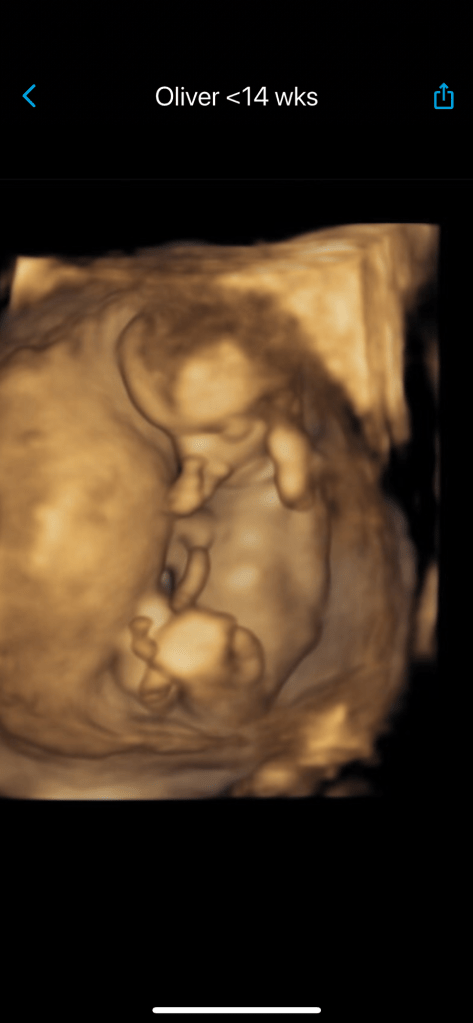

Here’s October 26th visit at 14 weeks.

I have to stop and Praise God who protected me all the way through this Fall as I traveled – no sicknesses, no bleeding, cramping, spotting. It was an amazing feeling every time I returned. The immunotherapy boost medication worked so I wasn’t getting my normal sickness after crowds, conferences, airplanes, and hotels. Mind you I wear masks on planes, in airports, and most of the time in crowded conference rooms. I am immune-compromised with my asthma, and now pregnant in my 40’s.